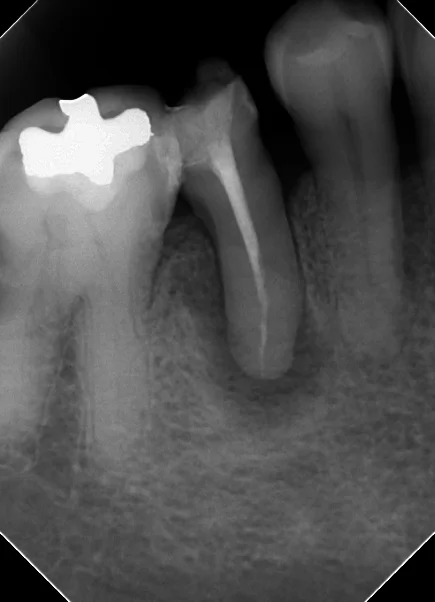

例えば、この方ですが・・・

閉鎖根管の治療には根気が必要|坂寄歯科医院(取手市藤代)

分かりますかね?

根の中央付近で神経の管が封鎖されているため、前の先生ではそれ以上に触れなかったのかそのままお薬を詰めている状態になっており、神経の管の下の方に何も入っていない状況になっています。